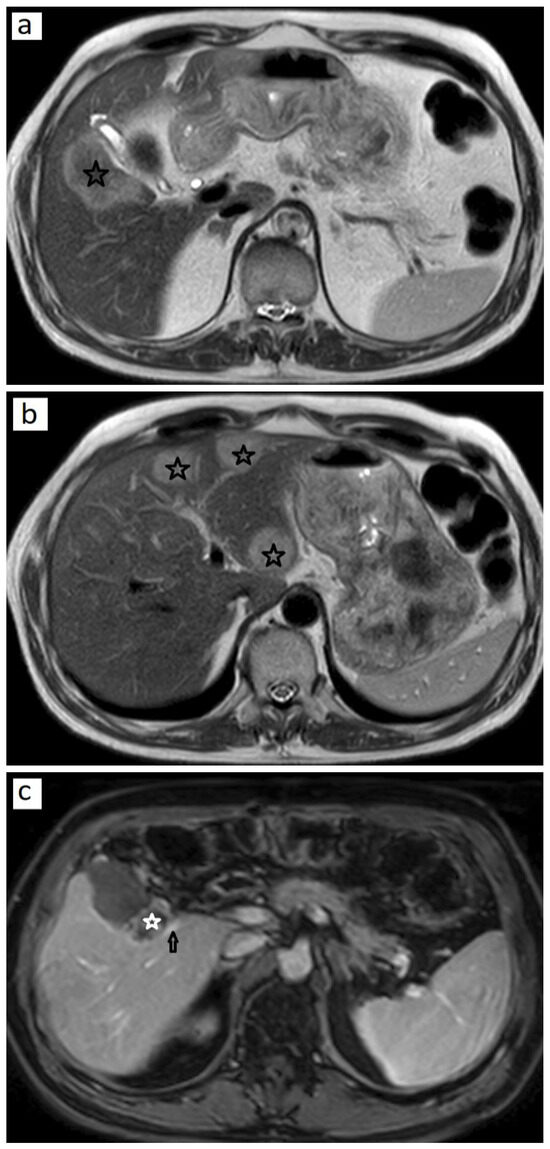

No incomplete ablation was observed in the first month follow-up after MWA. The rate of LTP after treatment was 7.4% (n=4) and the rate of IDR was 46.3% (n=25). In 46.3% (n=25) of the patients, total response was achieved (Figure 1).

Figure 1.

Local tumor progression in a 65-year-old patient with colon cancer. (a) T2-weighed image shows a hyperintense metastasis with a diameter of 3 cm in segment V near the gallbladder bed and portal vein branch, which was treated with microwave ablation therapy. (b) Three metastases in the left lobe (black asterisks), which were resected via lobectomy, are seen on T2-weighed image. (c) At 1-year follow-up, a local tumor progression (white asterisk) adjacent to a portal vein branch (arrow) is encountered on postcontrast T1-weighed image.